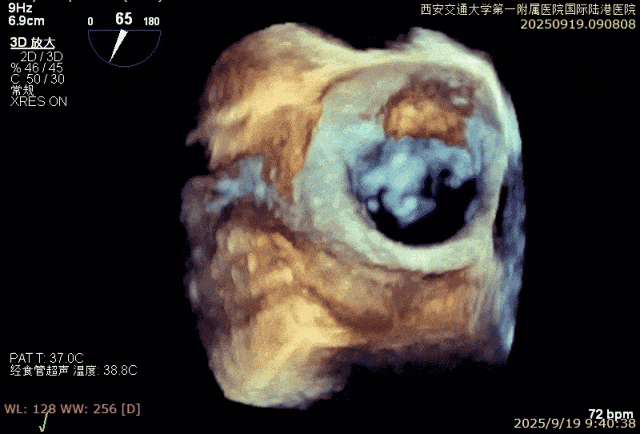

患者男性,69岁,术前TEE评估为FMR患者,因左室功能异常引发二尖瓣重度反流;后叶拴系,反流来源于整个2区,主要集中在2偏1、2偏3。患者瓣口面积约6.2cm²。房间隔可穿刺高度4.5cm。反流束宽度约19mm。AP径36.5mm。

经专家团队评估后决定于2区正中位置先植入一把XTR,植入后评估反流改善情况,如仍有反流,可调整第一把夹子放置于2区偏内,再于第一把夹子外侧植入第二枚夹子,改善对合和反流。

术中在超声引导下完成房间隔穿刺,将第一枚XTR在左房内完成终定位,2偏3区完成植入,夹合效果良好,即刻超声显示轻微反流,完成夹子释放,手术效果良好,手术圆满结束,患者术后6小时即实现床旁活动。